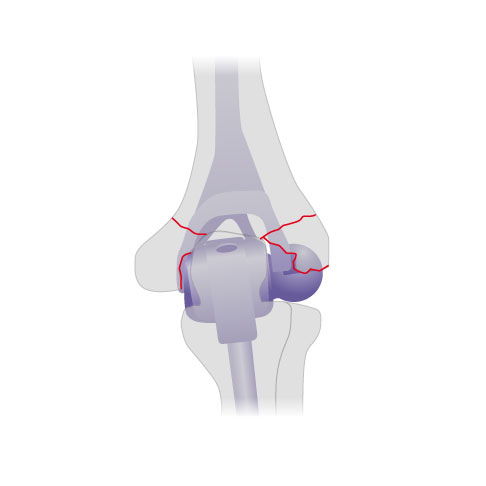

Auch bei einem akuten Bruch des unteren Oberarmknochens (distaler Humerus) bei älteren Patienten kann der Ellenbogenspezialist anstelle einer Knochenrekonstruktion direkt eine Ellenbogenprothesen einsetzen. Gerade bei älteren Patienten mit komplizierten Knochenbrüchen kann die Knochenheilung eingeschränkt sein. Der Einbau der Ellenbogenprothese hilft den Patienten, ihren Arm rasch wieder bewegen und belasten zu können.

Die Abbildung zeigt eine implantierte Ellenbogenprothese nach einem komplizierten Bruch des Ellenbogengelenks von hinten. Die roten Linien markieren die Frakturlinien. © Gelenk-Klinik

Der Operateur zementiert die Prothese in den nicht gebrochenen Knochenschaft ein. © Gelenk-Klinik